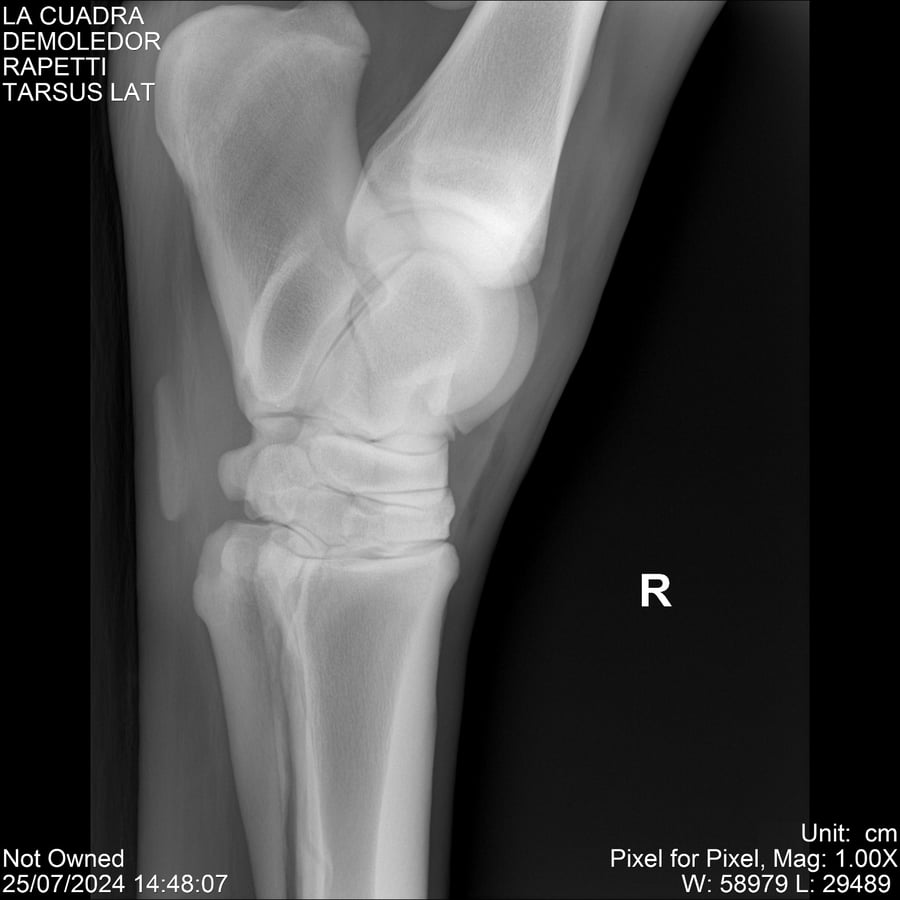

LOTE 14, DEMOLEDOR 🔥 🔥 🔥 Lote Anterior Volver al remate Lote Siguiente Ficha Contacto Montevideo - Ficha del Lote Identificador: #284454 Categoría: Yeguarizos Montevideo - 89 Visualizaciones ClicData Contacto Empresa: Abelenda N. R., Walter Hugo Nombre*: Teléfono* : E-mail* : Mensaje Enviar Registrese gratis Este contenido Exclusivo está disponible sólo para usuarios registrados Ingresar